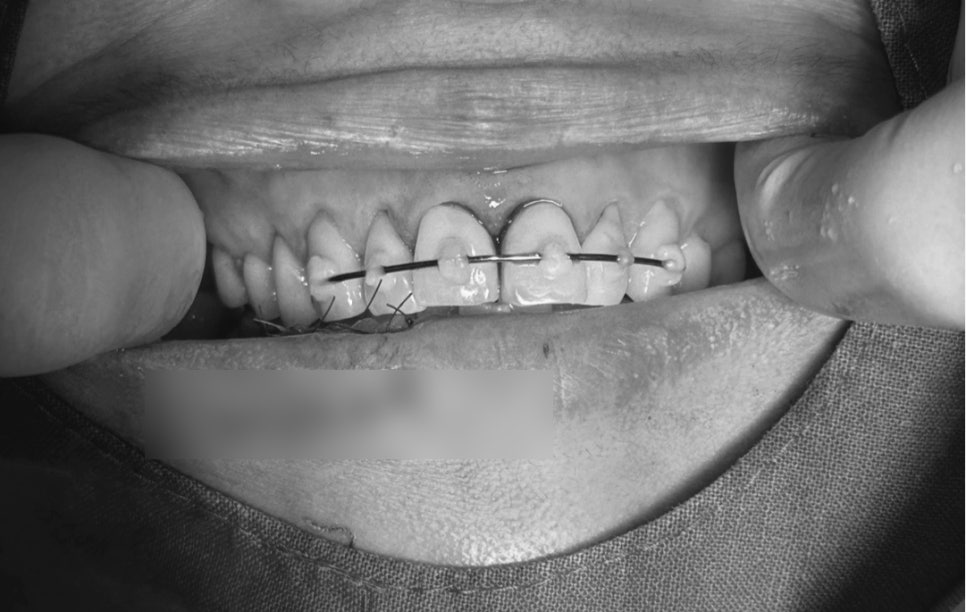

치조골 골절 및 앞니 고정장치

- 치조골 골절 & 앞니 고정술

충격으로 앞니가 뒤로 밀리거나 흔들리면,

반드시 제 위치로 되돌리고 일정 기간 고정해야 합니다.

이번 케이스에서도

부러진 잇몸뼈 제자리 정복

앞니 부목 지지대 고정 시술

이 이루어졌습니다.

이는 치아가 다시 안정적으로 뼈와 붙도록 돕는 과정입니다.

고정을 하지 않거나 늦어지면, 치아가 점점 더 움직이거나 신경이 괴사될 위험이 높습니다.